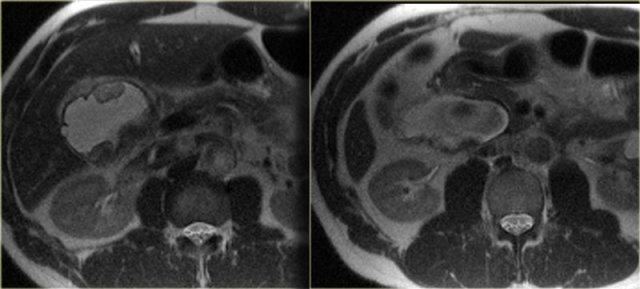

Bên trái là hình ảnh của một bệnh nhân mắc bệnh Caroli.

Lưu ý tình trạng giãn ống mật trong gan và đường kính bình thường của ống mật chủ (ống mật ngoài gan).

Đặc điểm điển hình của bệnh Caroli là giãn ống mật trong gan.

Tình trạng giãn có thể rất lớn và dạng túi như trong trường hợp bên trái, hoặc có thể có dạng tuyến tính.

Bên trái là hình ảnh CT của cùng bệnh nhân.

Lưu ý dấu hiệu chấm trung tâm và tổn thương theo phân thùy.

Bệnh nhân này có xơ gan kèm lách to do tăng áp lực tĩnh mạch cửa.

Giãn ống mật ngoài gan hiện diện trong 53% các trường hợp, thứ phát do viêm đường mật và sự di chuyển của sỏi hoặc bùn mật.

Đây là các dấu hiệu thứ phát, không phải là một phần của bệnh nguyên phát.